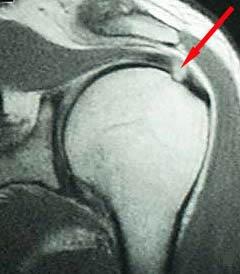

Rotatorenmanschettenriß in der Kernspintomographie

Der Patient berichtet, dass er beim Volleyballspiel beim Überkopfaufschlag eine Schultergelenksverrenkung (Luxation) erlitten habe. Er habe bereits zuvor leichte Beschwerden gehabt. In der Kernspintomographie zeigte sich ein Sehnenabriss an der Supraspinatussehne wie auch eine Kapselverletzung am vorderen unteren Gelenk. Arthroskopisches Vorgehen mit Rekonstruktion der Läsionen. Der Patient demonstriert nach 6 Monaten im Januar 2022 eine stabile Schulter im Rahmen der Liegestütze. Eine Wiederaufnahme des Volleyballspielens ist im Weiteren geplant.

62-jährige Patientin mit erheblichen Schmerzen und vollschichtiger Supraspinatussehnenablösung. Die Sehne war sehr weit zurückgezogen, bereits sichtbar auf der präoperativen Kernspintomographie und ließ sich auch intraoperativ nicht so weit mobilisieren. Eine Rekonstruktion war spannungsarm nicht möglich. Es wurde ein mit Flüssigkeit gefüllter Ballon unter dem Schulterdach arthroskopisch gestützt eingeschoben und entfaltet. Dieser Ballon führt neben einer Abstandshaltung zum Schulterdach zu einer Fremdköperreaktion und Membranbildung. Durch die anhaltende Trainingstherapie konnte die Patientin trotz des Defektes eine Rezentrierung des Gelenkes mit sehr guter anhaltender Funktion erzielen.

Infraspinatus und Subscapularis intakt

Supraspinatusdefekt